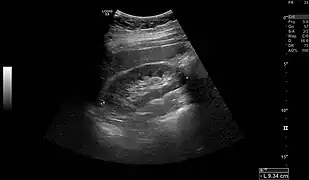

Normal adult right kidney as seen on abdominal ultrasound with a pole to pole measurement of 9.34 cm

Imaging

Renal ultrasonography is essential in the diagnosis and management of kidney-related diseases.[46] Other modalities, such as CT and MRI, should always be considered as supplementary imaging modalities in the assessment of renal disease.[46]